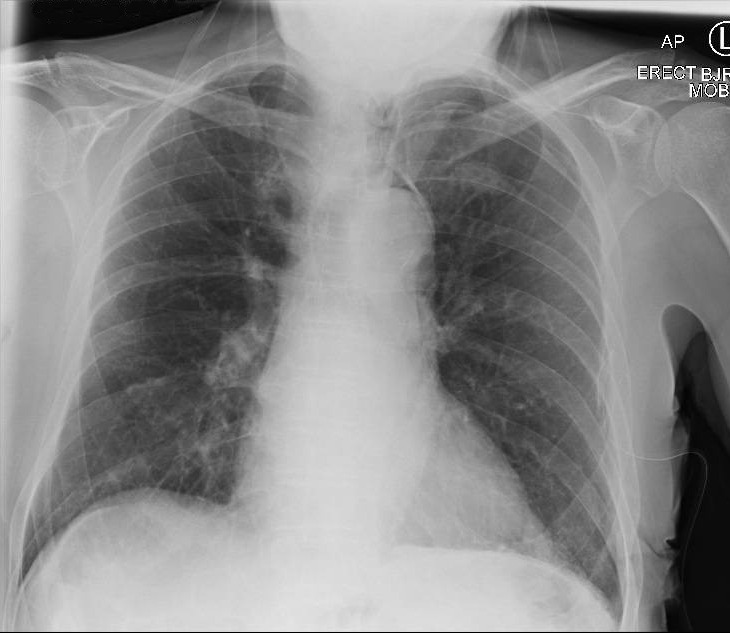

Secondary pneumothoraces can be the first presentation of pleural malignancies and may also complicate their course. They are often associated with prolonged air leaks, and cardiothoracic intervention can be required. https://bit.ly/3DEvPem.

Abstract Image